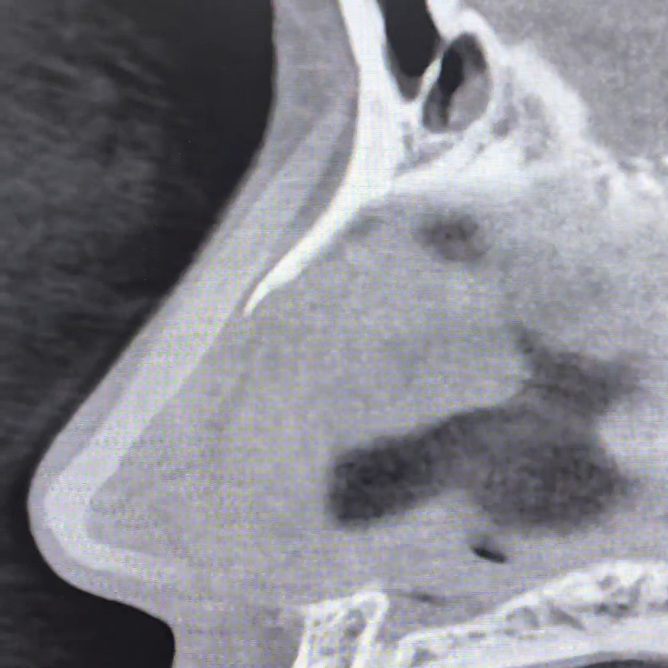

2 ตรวจดูทรงซิลิโคน จมูกไม่สวยซักที CTบอกได้ เพราะ การตรวจด้วยเครื่องเอกซเรย์คอมพิวเตอร์ความละเอียดสูง สามารถบอกได้ว่าปัญหาความไม่สวยเกิดจากอะไร ทรงSILICONEจมูก ยาวหรือสั้นเกินไป SILICONEตรงหรือโก่ง หัวใหญ่หัวเล็ก การตรวจด้วยเครื่องเอกซเรย์คอมพิวเตอร์ความละเอียดสูง บอกได้ทั้งหมด จะเห็นว่ารูปทรงของSILICONE เมื่อเสริมเข้ามาจริงๆแล้ว ยังต้องมีการปรับตัวให้เข้ากับเนื้อเยื่อรอบด้านทำให้ไม่สามารถประเมินจากภายนอกเพียงอย่างเดียวได้

3 ความเสี่ยงของการทะลุ ในกรณี มีการดันของซิลิโคนมากเกินไปจนผิวหนังบางขึ้น การตรวจด้วยเครื่องเอกซเรย์คอมพิวเตอร์ความละเอียดสูง สามารถบอกได้ โดยเฉพาะอย่างยิ่งการทะลุจากด้านในรูจมูก พราะส่วนใหญ่ของการทะลุไม่ได้เกิดบริเวณผิวด้านนอก แต่เกิดด้านในรูจมูก ซึ่งยากต่อการตรวจสอบ